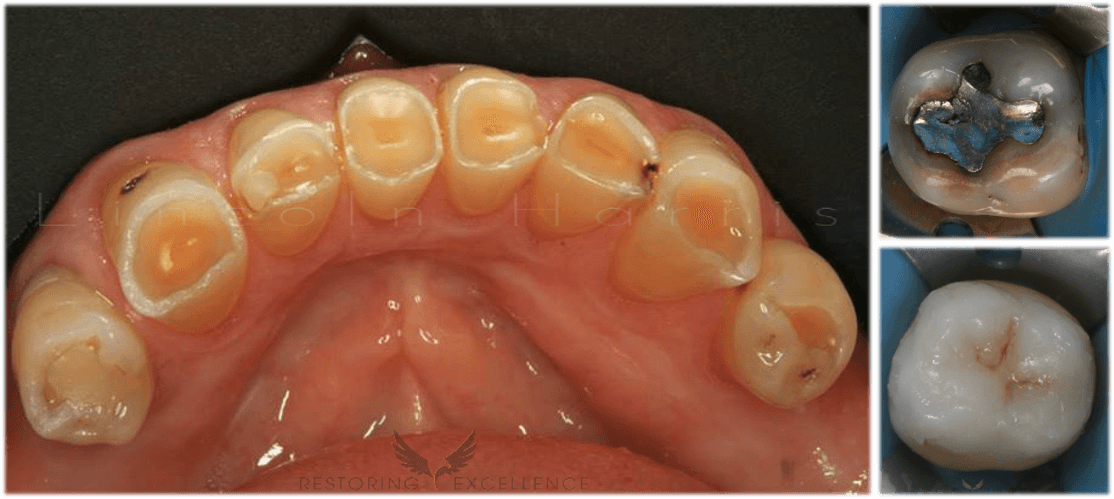

Replacing Composite FPD

Sep 2, 2015

Treatment Planning Bridge Cases composite fpd Dentist Dentistry Lincoln Harris Restoring Excellence